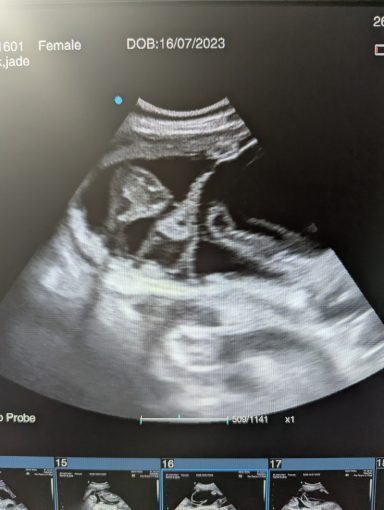

Ultrasound pregnancy scanning is a safe, non-invasive way to confirm pregnancy in dogs and cats, offering breeders and pet owners peace of mind and vital information to support responsible care. It allows us to detect gestational sacs, assess foetal development, and estimate litter size—all while ensuring the wellbeing of the animal.

Gallery